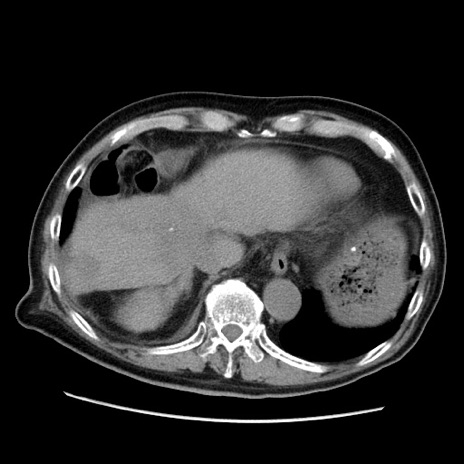

症例21(横断像)

【症例】70歳代男性

【主訴】腹痛

【現病歴】肝硬変・肝細胞癌にてかかりつけの方。約9時間前に食後より腹痛出現。症状が徐々に増悪し、嘔吐出現したため来院。

【既往歴】肝硬変、肝細胞癌(RFA、TACE後)

【身体所見】意識清明、表情苦悶様、BT 36℃、BP 129/78mmHg、P 88bpm、SpO2 97%(RA)、右上腹部から心窩部にかけて圧痛あり、反跳痛なし、筋性防御あり。

【データ】WBC 5800、CRP 0.16